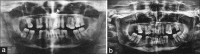

Context: Odontogenic cysts are among the most common lesions to affect the oral and maxillofacial region. Cysts are capable of causing significant bony disfigurement, tooth displacement and pathological fractures. Several surgical approaches exist for the management of larger cysts of the jaws. These include enucleation, marsupialization and decompression.

Settings and design: Decompression technique was used for the treatment of 10 cases of odontogenic cysts in the study. Incisional biopsies of cystic lining (pretreatment) and corresponding excisional biopsies (posttreatment) were received for histopathologic and immunohistochemical examination.

Results: Overall, radicular cysts, dentigerous cysts, and sialo-odontogenic cyst contained fewer Ki-67 + cells than odontogenic keratocysts. The average scores were found to be 2.2 and 1 for before and after decompression, respectively. A statistically significant difference was observed between the two groups. The two-tailed P value was found to be <0.0001. The confidence interval was found to be 95%.

Conclusions: The proliferative activity evaluated by Ki-67 marker was greater in predecompression epithelial lining compared to postdecompression. Our study infers that proliferative rate of the cystic epithelial lining is significantly diminished after decompression.